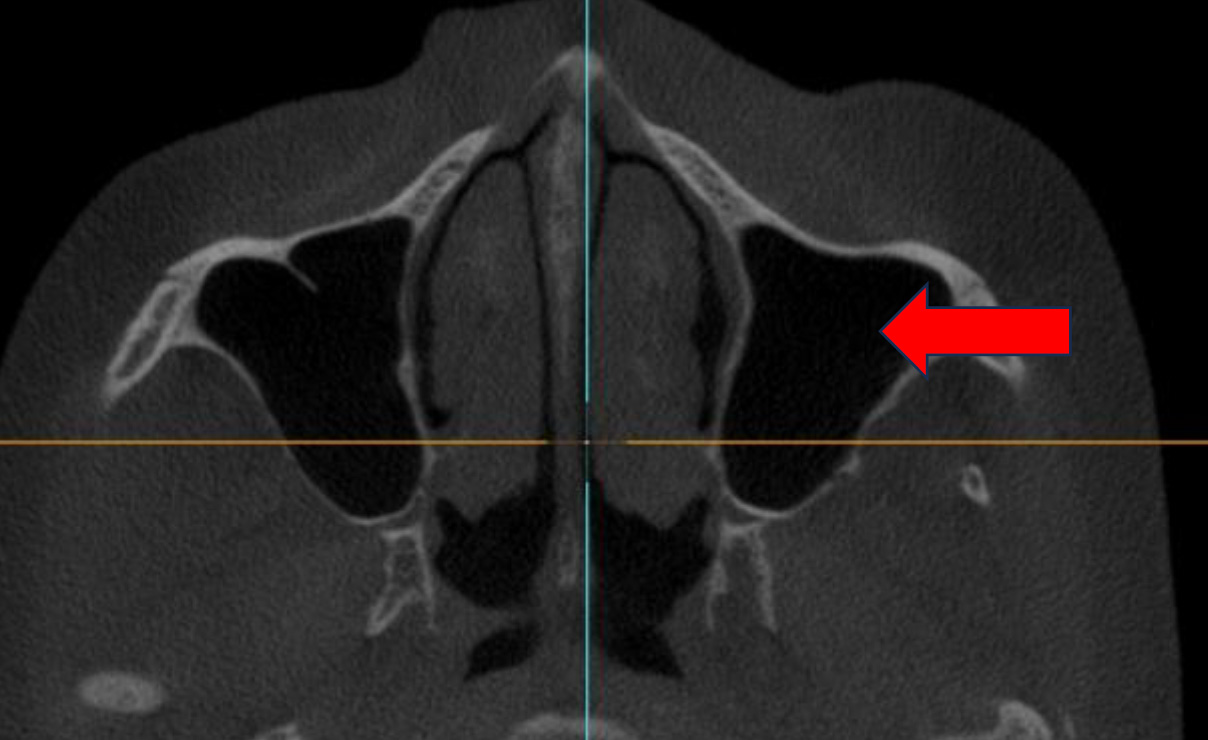

RESUME

CBCT March 2023